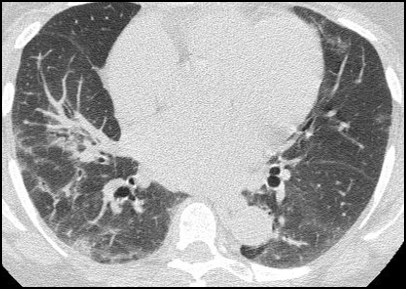

HRCT: PROBABLE UIP PATTERN5,6,18

- Subpleural, basal predominance

- Heterogeneous distribution of areas of normal lung and traction bronchiectasis/bronchiolectasis

- Reticulation accompanied by traction bronchiectasis/bronchiolectasis

- Some mild GGO

Subpleural sparing absent

Image used with permission from the American Thoracic Society. © 2014. Raghu G et al.6